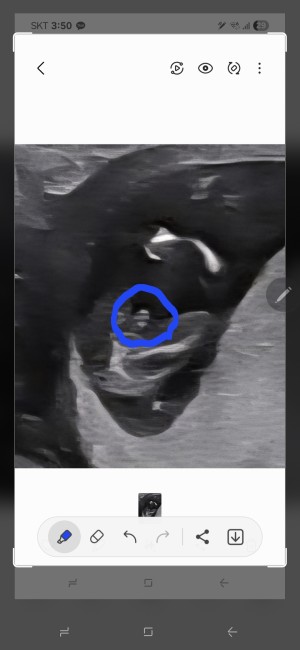

성별알게되었어요^^

사랑해요♡

2025-10-07